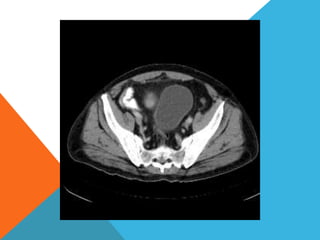

El paciente presentó síntomas de sangrado digestivo y pérdida de peso. Exámenes revelaron gastritis crónica asociada a H. pylori. Un tumor fue descubierto en una colonoscopia normal. La cirugía removió un tumor fibroide solitario, una rara neoplasia mesenquimal que usualmente crece lento y tiene bajo potencial de malignidad. El pronóstico después de la remoción quirúrgica es generalmente bueno.